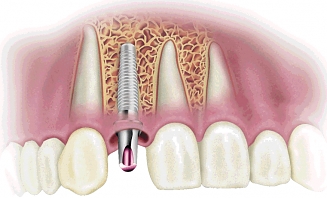

Zubní implantát je umělá náhražka původního zubu, která přebírá jeho funkci. Využívá se u ztráty trvalých zubů a jeho předností je, že nevyžaduje broušení okolních zubů.

Zubní implantát nahradí poškozený kořen kořenem umělým a to u jednoho, či více chybějících zubů, aniž by bylo nutno obrousit ostatní zdravé zuby, jako se děje právě v případech protéz. Zubní implantáty je pak základem pro další zubní náhradu.